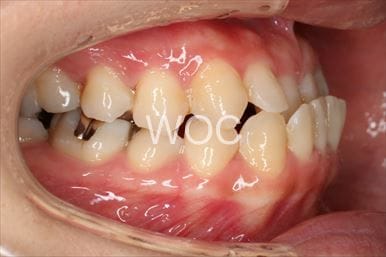

八重歯・叢生上のみ舌側矯正、下はエッジワイズ装置

上は舌側矯正を希望。ガタガタ(叢生)が強い。上顎右側中切歯・側切歯が歯科治療で連結してあったがそれを除去してから治療開始しました。

- 年齢:23歳女性

- 主訴:上下前歯のガタガタが気になる

- 基本矯正料金:103万円

- 治療期間:2年2ヶ月

- 非抜歯

-